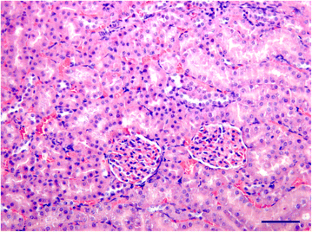

The effects of Agaricus blazei intake on the lipid profile of animals fed a hypercholesterolemic diet were evaluated. Thirty-two female Fisher rats were divided into four groups and given the standard AIN-93 M diet (C), this diet + 1 % A. blazei (CAb), a hypercholesterolemic diet with 25 % soybean oil and 1 % cholesterol (H) or this diet + 1 % A. blazei (HAb) for 6 weeks. Food intake, weight gain, liver and serum lipid profiles, activity of aminotransferases [alanine aminotransferase (ALT) and aspartate aminotransferase (AST)], and creatinine and urea levels as well as abdominal fat weight were measured. Histological analysis of kidney and liver tissue was also performed. The HAb group had a higher food intake, but a lower weight gain as compared to group H. This resulted in a significant decrease in abdominal fat weight, to values close to those of groups C and CAb. Supplementing the hypercholesterolemic diet with A. blazei promoted a significant reduction in total and non-HDL cholesterol, as well as in the atherogenic index, as compared to group H, and this effect was more pronounced in the serum. There was no hepatotoxic effect caused by the supplementation of the diets with the mushroom. We conclude that in our experimental model and in the concentration used, A. blazei was effective in improving the lipid profile of the animals.

Fig. 1

Fig. 2

Fig. 3